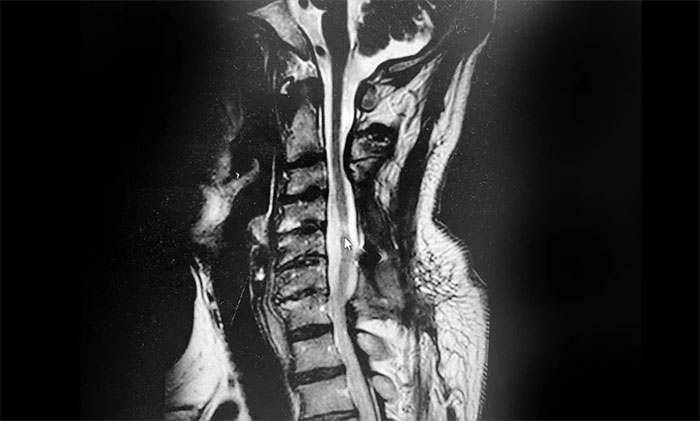

到就近醫(yī)院救治,急診查頸椎CT示:患者頸3-7椎體略變扁、頸椎反弓、項(xiàng)韌帶鈣化。頸椎脊髓損傷發(fā)生四肢癱瘓者,往往病情嚴(yán)重,常發(fā)生呼吸系統(tǒng)并發(fā)癥,病死率高,對(duì)其治療刻不容緩。其后,老劉轉(zhuǎn)外院立即接受了頸椎后路減壓融合內(nèi)固定手術(shù)。

▲患者頸髓損傷、頸椎反弓

在外院經(jīng)抗感染、營(yíng)養(yǎng)神經(jīng)等治療后,老劉病情趨于穩(wěn)定,但仍然遺留下高位截癱,四肢幾乎無(wú)法活動(dòng),只能長(zhǎng)期臥床,留置導(dǎo)尿管排尿。